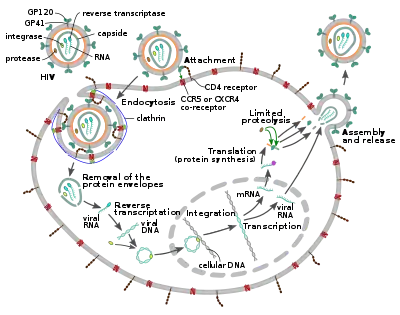

Replication cycle

Entry to the cell

The HIV virion enters macrophages and CD4+ T cells by the adsorption of glycoproteins on its surface to receptors on the target cell followed by fusion of the viral envelope with the target cell membrane and the release of the HIV capsid into the cell.[58][59]

Entry to the cell begins through interaction of the trimeric envelope complex (gp160 spike) on the HIV viral envelope and both CD4 and a chemokine co-receptor (generally either CCR5 or CXCR4, but others are known to interact) on the target cell surface.[58][59] Gp120 binds to integrin α4β7 activating LFA-1, the central integrin involved in the establishment of virological synapses, which facilitate efficient cell-to-cell spreading of HIV-1.[60] The gp160 spike contains binding domains for both CD4 and chemokine receptors.[58][59]

The first step in fusion involves the high-affinity attachment of the CD4 binding domains of gp120 to CD4. Once gp120 is bound with the CD4 protein, the envelope complex undergoes a structural change, exposing the chemokine receptor binding domains of gp120 and allowing them to interact with the target chemokine receptor.[58][59] This allows for a more stable two-pronged attachment, which allows the N-terminal fusion peptide gp41 to penetrate the cell membrane.[58][59] Repeat sequences in gp41, HR1, and HR2 then interact, causing the collapse of the extracellular portion of gp41 into a hairpin shape. This loop structure brings the virus and cell membranes close together, allowing fusion of the membranes and subsequent entry of the viral capsid.[58][59]

After HIV has bound to the target cell, the HIV RNA and various enzymes, including reverse transcriptase, integrase, ribonuclease, and protease, are injected into the cell.[58] During the microtubule-based transport to the nucleus, the viral single-strand RNA genome is transcribed into double-strand DNA, which is then integrated into a host chromosome.

HIV can infect dendritic cells (DCs) by this CD4-CCR5 route, but another route using mannose-specific C-type lectin receptors such as DC-SIGN can also be used.[61] DCs are one of the first cells encountered by the virus during sexual transmission. They are currently thought to play an important role by transmitting HIV to T cells when the virus is captured in the mucosa by DCs.[61] The presence of FEZ-1, which occurs naturally in neurons, is believed to prevent the infection of cells by HIV.[62]

HIV-1 entry, as well as entry of many other retroviruses, has long been believed to occur exclusively at the plasma membrane. More recently, however, productive infection by pH-independent, clathrin-mediated endocytosis of HIV-1 has also been reported and was recently suggested to constitute the only route of productive entry.[63][64][65][66][67]

Replication and transcription

Shortly after the viral capsid enters the cell, an enzyme called reverse transcriptase liberates the positive-sense single-stranded RNA genome from the attached viral proteins and copies it into a complementary DNA (cDNA) molecule.[68] The process of reverse transcription is extremely error-prone, and the resulting mutations may cause drug resistance or allow the virus to evade the body's immune system. The reverse transcriptase also has ribonuclease activity that degrades the viral RNA during the synthesis of cDNA, as well as DNA-dependent DNA polymerase activity that creates a sense DNA from the antisense cDNA.[69] Together, the cDNA and its complement form a double-stranded viral DNA that is then transported into the cell nucleus. The integration of the viral DNA into the host cell's genome is carried out by another viral enzyme called integrase.[68]

The integrated viral DNA may then lie dormant, in the latent stage of HIV infection.[68] To actively produce the virus, certain cellular transcription factors need to be present, the most important of which is NF-κB (nuclear factor kappa B), which is upregulated when T cells become activated.[70] This means that those cells most likely to be targeted, entered and subsequently killed by HIV are those actively fighting infection.

During viral replication, the integrated DNA provirus is transcribed into RNA, some of which then undergo RNA splicing to produce mature messenger RNAs (mRNAs). These mRNAs are exported from the nucleus into the cytoplasm, where they are translated into the regulatory proteins Tat (which encourages new virus production) and Rev. As the newly produced Rev protein is produced it moves to the nucleus, where it binds to full-length, unspliced copies of virus RNAs and allows them to leave the nucleus.[71] Some of these full-length RNAs function as new copies of the virus genome, while others function as mRNAs that are translated to produce the structural proteins Gag and Env. Gag proteins bind to copies of the virus RNA genome to package them into new virus particles.[72]

Assembly and release

The final step of the viral cycle, assembly of new HIV-1 virions, begins at the plasma membrane of the host cell. The Env polyprotein (gp160) goes through the endoplasmic reticulum and is transported to the Golgi apparatus where it is cleaved by furin resulting in the two HIV envelope glycoproteins, gp41 and gp120.[84] These are transported to the plasma membrane of the host cell where gp41 anchors gp120 to the membrane of the infected cell. The Gag (p55) and Gag-Pol (p160) polyproteins also associate with the inner surface of the plasma membrane along with the HIV genomic RNA as the forming virion begins to bud from the host cell. The budded virion is still immature as the gag polyproteins still need to be cleaved into the actual matrix, capsid and nucleocapsid proteins. This cleavage is mediated by the packaged viral protease and can be inhibited by antiretroviral drugs of the protease inhibitor class. The various structural components then assemble to produce a mature HIV virion.[85] Only mature virions are then able to infect another cell.

Spread within the body

The classical process of infection of a cell by a virion can be called "cell-free spread" to distinguish it from a more recently recognized process called "cell-to-cell spread".[86] In cell-free spread (see figure), virus particles bud from an infected T cell, enter the blood or extracellular fluid and then infect another T cell following a chance encounter.[86] HIV can also disseminate by direct transmission from one cell to another by a process of cell-to-cell spread, for which two pathways have been described. Firstly, an infected T cell can transmit virus directly to a target T cell via a virological synapse.[60][87] Secondly, an antigen-presenting cell (APC), such as a macrophage or dendritic cell, can transmit HIV to T cells by a process that either involves productive infection (in the case of macrophages) or capture and transfer of virions in trans (in the case of dendritic cells).[88] Whichever pathway is used, infection by cell-to-cell transfer is reported to be much more efficient than cell-free virus spread.[89] A number of factors contribute to this increased efficiency, including polarised virus budding towards the site of cell-to-cell contact, close apposition of cells, which minimizes fluid-phase diffusion of virions, and clustering of HIV entry receptors on the target cell towards the contact zone.[87] Cell-to-cell spread is thought to be particularly important in lymphoid tissues where CD4+ T cells are densely packed and likely to interact frequently.[86] Intravital imaging studies have supported the concept of the HIV virological synapse in vivo.[90] The many spreading mechanisms available to HIV contribute to the virus' ongoing replication in spite of anti-retroviral therapies.[86][91]